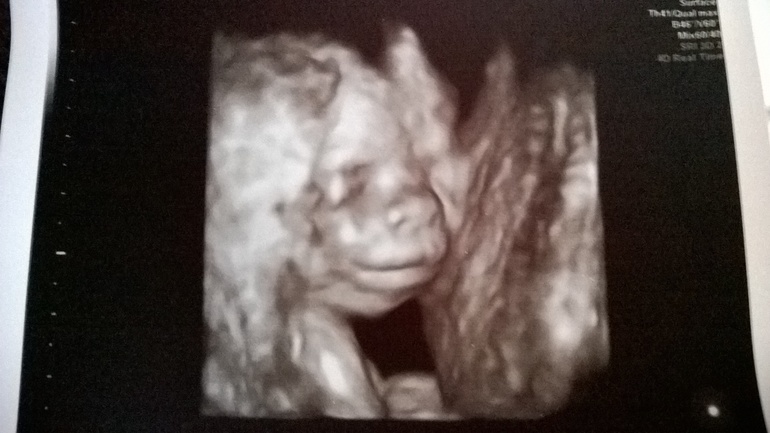

Фотопуз:

Детеныш: с 21 апреля активно общается со мной и папой ( остальных пока боится). До этого были непонятные «бульканья», а сейчас уже ни с чем не спутаешь )) Особенно активный вечером и в обед.

А вот наш Максим Дмитриевич (пока так. Как родится - посмотрим как лучше назвать )